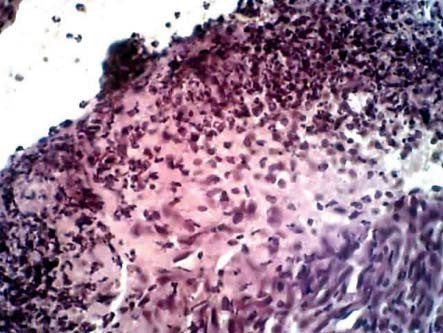

К 4-м сут лечения морфологическая картина ран у животных 2-й группы характеризовалась тем, что поверхностный лейкоцитарно-некротический слой был тонким, а диффузная лейкоцитарная воспалительная инфильтрация мягких тканей раны была снижена. Грануляционная ткань содержала достаточно большое количество лимфоцитов и нейтрофилов, имелись незрелые клетки фибробластического ряда. Новообразованных кровеносных сосудов небольшое количество, определялись лимфостазы. Сохранялась необильная межмышечная макрофагально-лимфоцитарная инфильтрация, по периферии прослеживались единичные фибробласты (рис. 2).

Рис. 2. Морфологическая картина раны при лечении диметилсульфоксидом на 4-е сут от начала наблюдения. Наблюдается выраженная нейтрофильная инфильтрация раны с интерстициальным отеком, в глубине – формирование грануляционной ткани. Окраска гематоксилин-эозином, ок. х7, об. х40